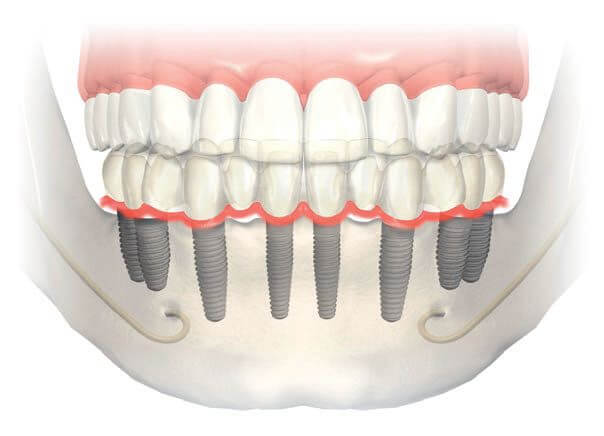

Bunlardan en uygununa karar verildikten sonra çene kemiğine implant yerleştirilir. İmplant tedavisi bir kişinin bir ya da daha fazla dişini kaybettiğinde ve yerine yeni diş yerleştirilmesini istediğinde gerçekleştirilen bir tedavi yöntemidir. Implant diş tedavisi iki aşamadan oluşmaktadır. İmplant tedavisinin süresi yapılacak olan implant sayısına ve hastanın çene kemiğine bağlı olarak yarım saat ile birkaç saat arasında da değişebilir.

İmplant tedavisi ne kadar sürer konusu ise çene kemiğinin durumuna ve yapılan implantın uyumuna göre faklılık gösterir. İmplant operasyonunda kullanılan dikişlerin kendinden erime özelliğine sahip olması tedaviyi bir günde de gerçekleştirme imkanı sunabilmektedir. Bu aşamalarda ise yapılacak olan implant tedavisi eğer ki tek bir operasyon olacak ise bu işlem yine hastanın durumunda göre. İmplant tedavisi cerrahi bir operasyonla yapılmaktadır.